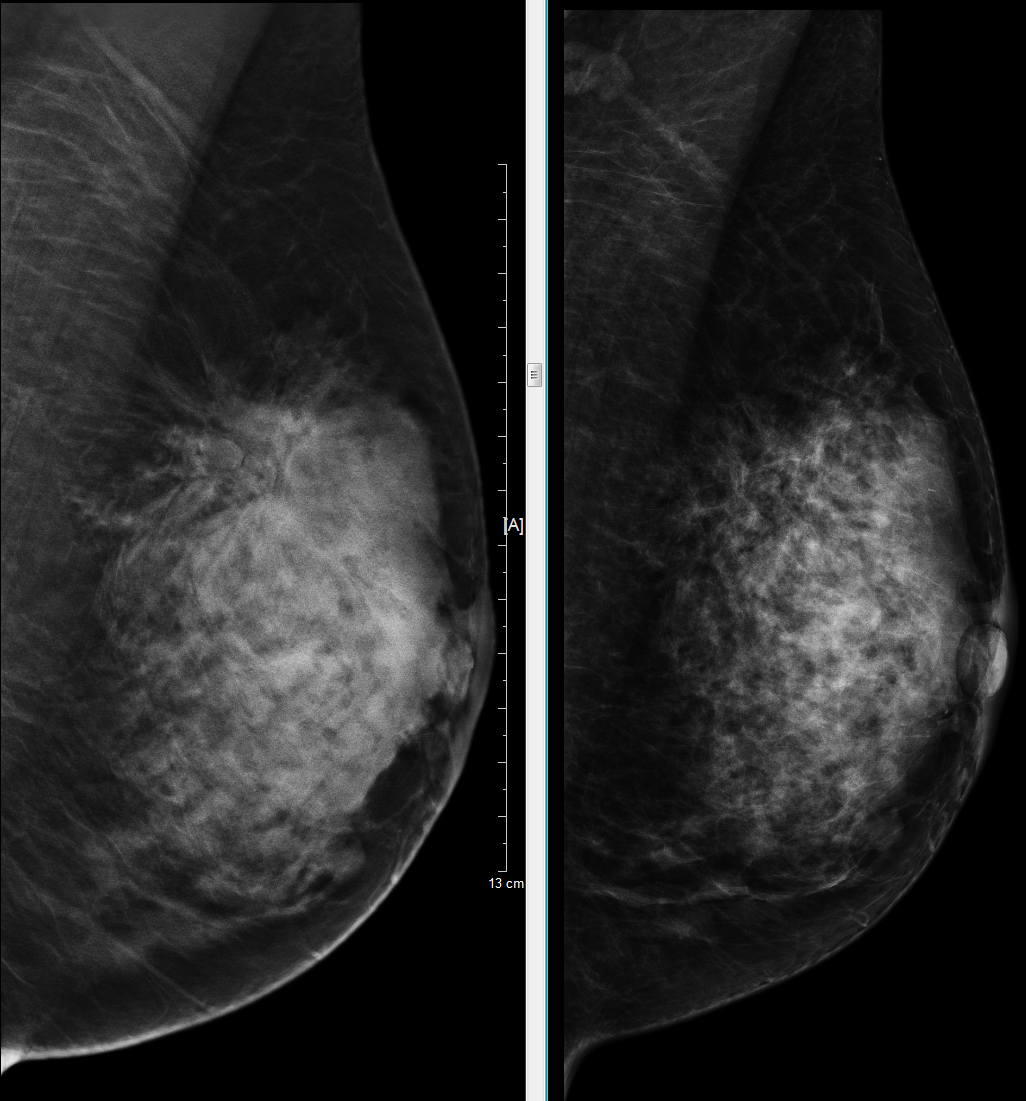

随着乳腺X线检查技术的不断普及,越来越多临床触诊甚至超声检查阴性的乳腺隐匿性病变被发现。对于部分临床、超声隐匿性乳腺病灶不能对疾病的良恶性进行有效判断时,乳腺X线立体定位活检技术就能通过穿刺活检技术对病灶病理性质以及类型进行直接明确诊断,由于乳腺X线立体定位穿刺活检术与手术病理符合率高,有利于临床进一步制订治疗方案,可以减少过度手术或把握手术最佳时机。